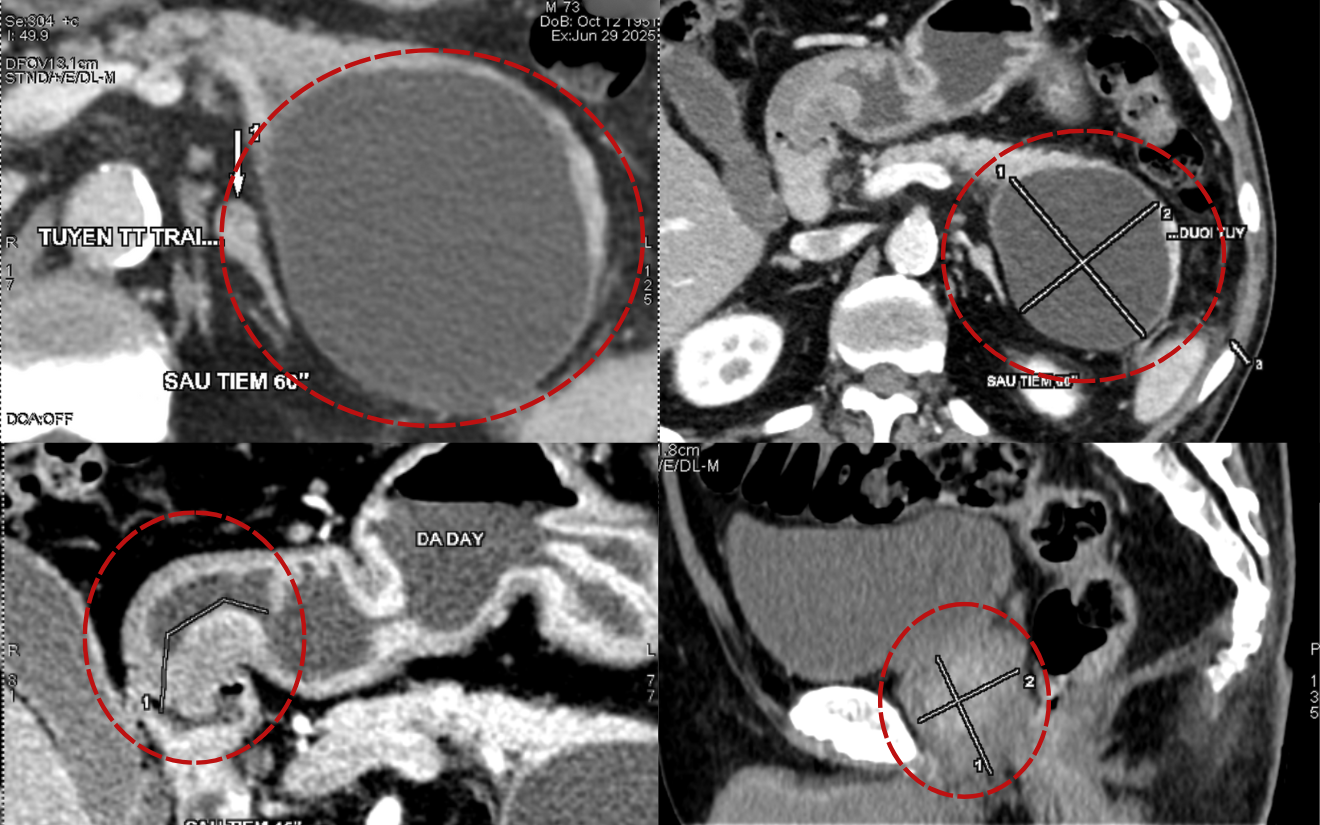

Bệnh nhân Phạm T, 76 tuổi, thăm khám tại BVĐK Hồng Ngọc trong tình trạng đau nóng râm ran vùng thượng vị, chán ăn, mệt mỏi. Kết quả nội soi và chụp CT phát hiện bệnh nhân có tổn thương tiêu hóa đa cơ quan: tổn thương loét vùng hang vị dạ dày, ung thư đại tràng sigma, và có nang tụy đường kính khoảng 10cm. Đây là một bệnh nhân tuổi cao, có nhiều bệnh lý nền phức tạp như đái tháo đường biến chứng suy thận, hẹp mạch vành, tăng huyết áp, rối loạn mỡ máu, viêm gan B… khiến việc điều trị gặp nhiều thách thức. Do vậy bệnh nhân đã được hội chẩn liên chuyên khoa để đề ra các biện pháp điều trị tối ưu nhất.

Kết quả chụp CT phát hiện bệnh nhân có tổn thương tiêu hóa đa cơ quan